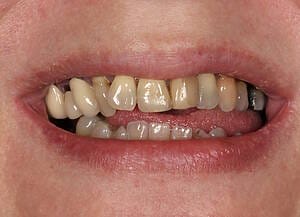

Natalie arrived at Wimpole Street Dental Clinic facing an extremely challenging dental situation. She had several missing and damaged teeth, infections in the bone, and significant bite issues caused by a long-term tongue habit. On top of that, she was a smoker and had developed a strong dental phobia over the years, making it difficult for her to seek help sooner.

Her case was not straightforward, but it was clear that the right care could offer a completely new beginning. She was referred to Prof Dr Christian Mehl, a leading expert in dental implantology, who partnered with Mr George Leventi of Aion Dental to deliver a highly personalised and technically advanced treatment plan.